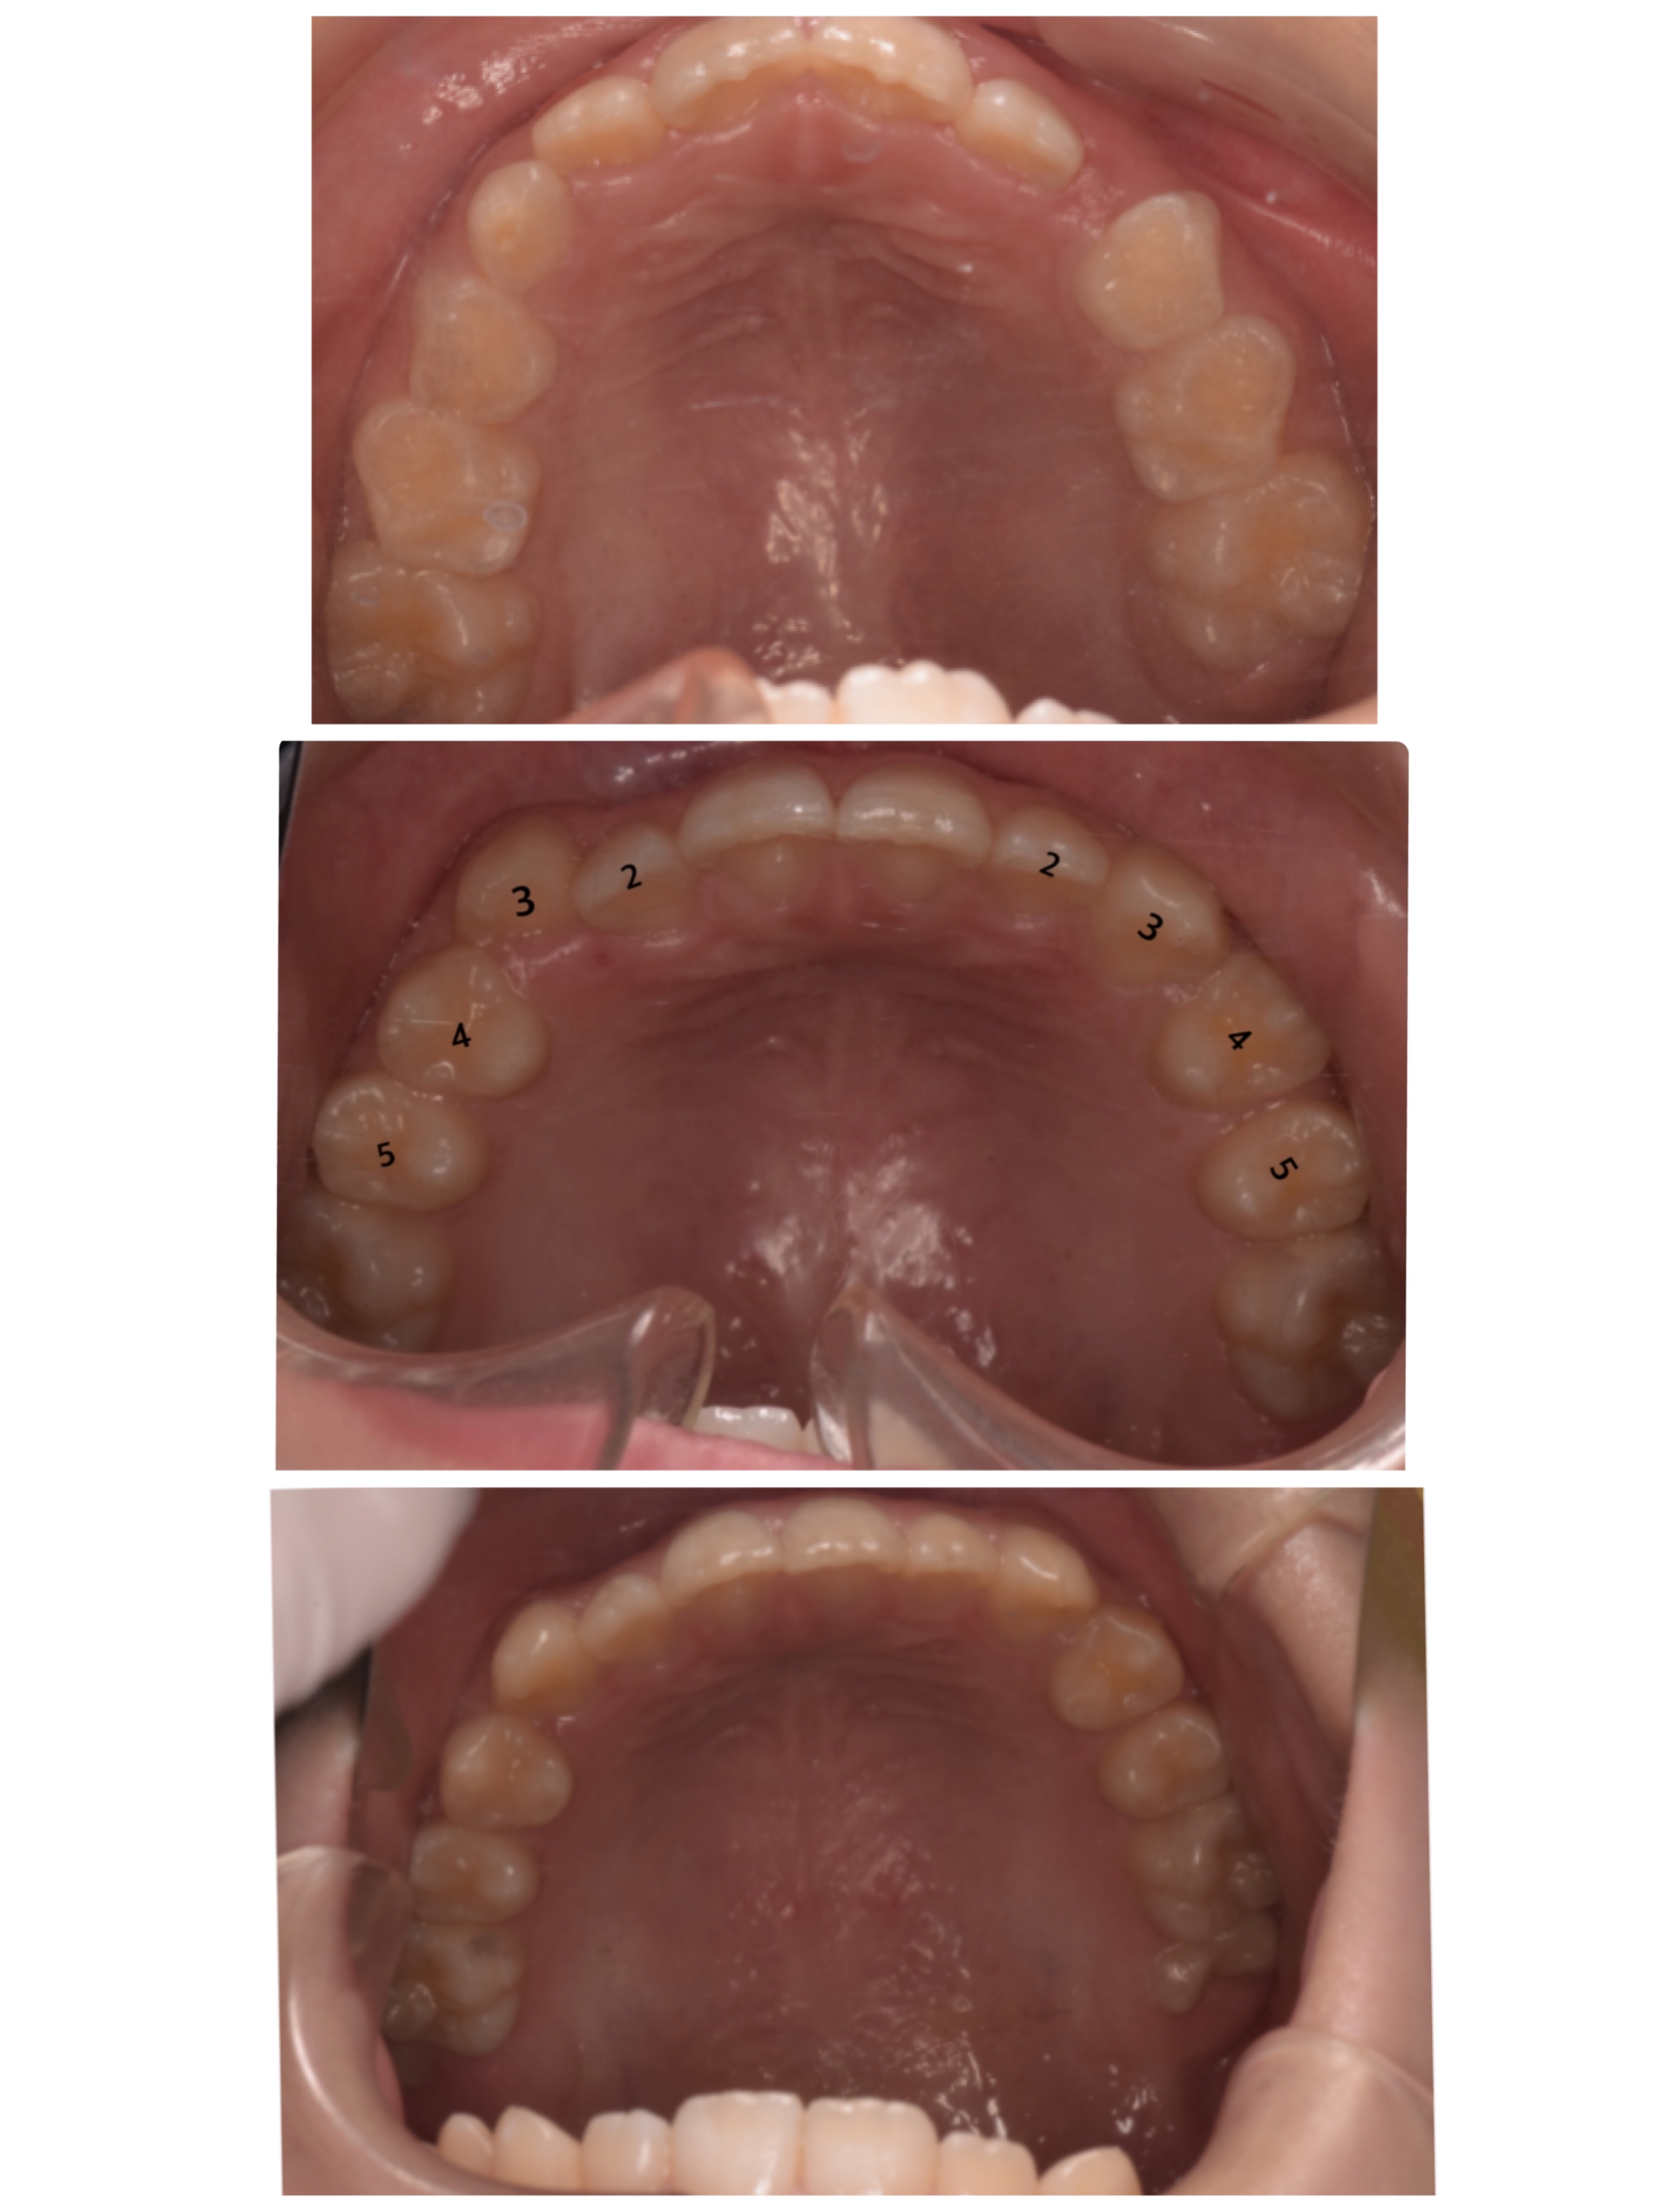

お口の中のお写真も見ていくとまだ下の歯は重なりがありますが、少しずつその重なりも少なくなって来ています。

歯と歯の間のスペースも少し広がって来ているのでもっと綺麗に並んでくれそうかな?と思います☺︎

お子様のプレート装置はブラケット矯正やマウスピース矯正とは少し違い、歯を直接動かすわけではなく顎のスペースを広げて並ぶようにする矯正装置なので少しずつ歯が並んでいくのを見守っていく形になります。